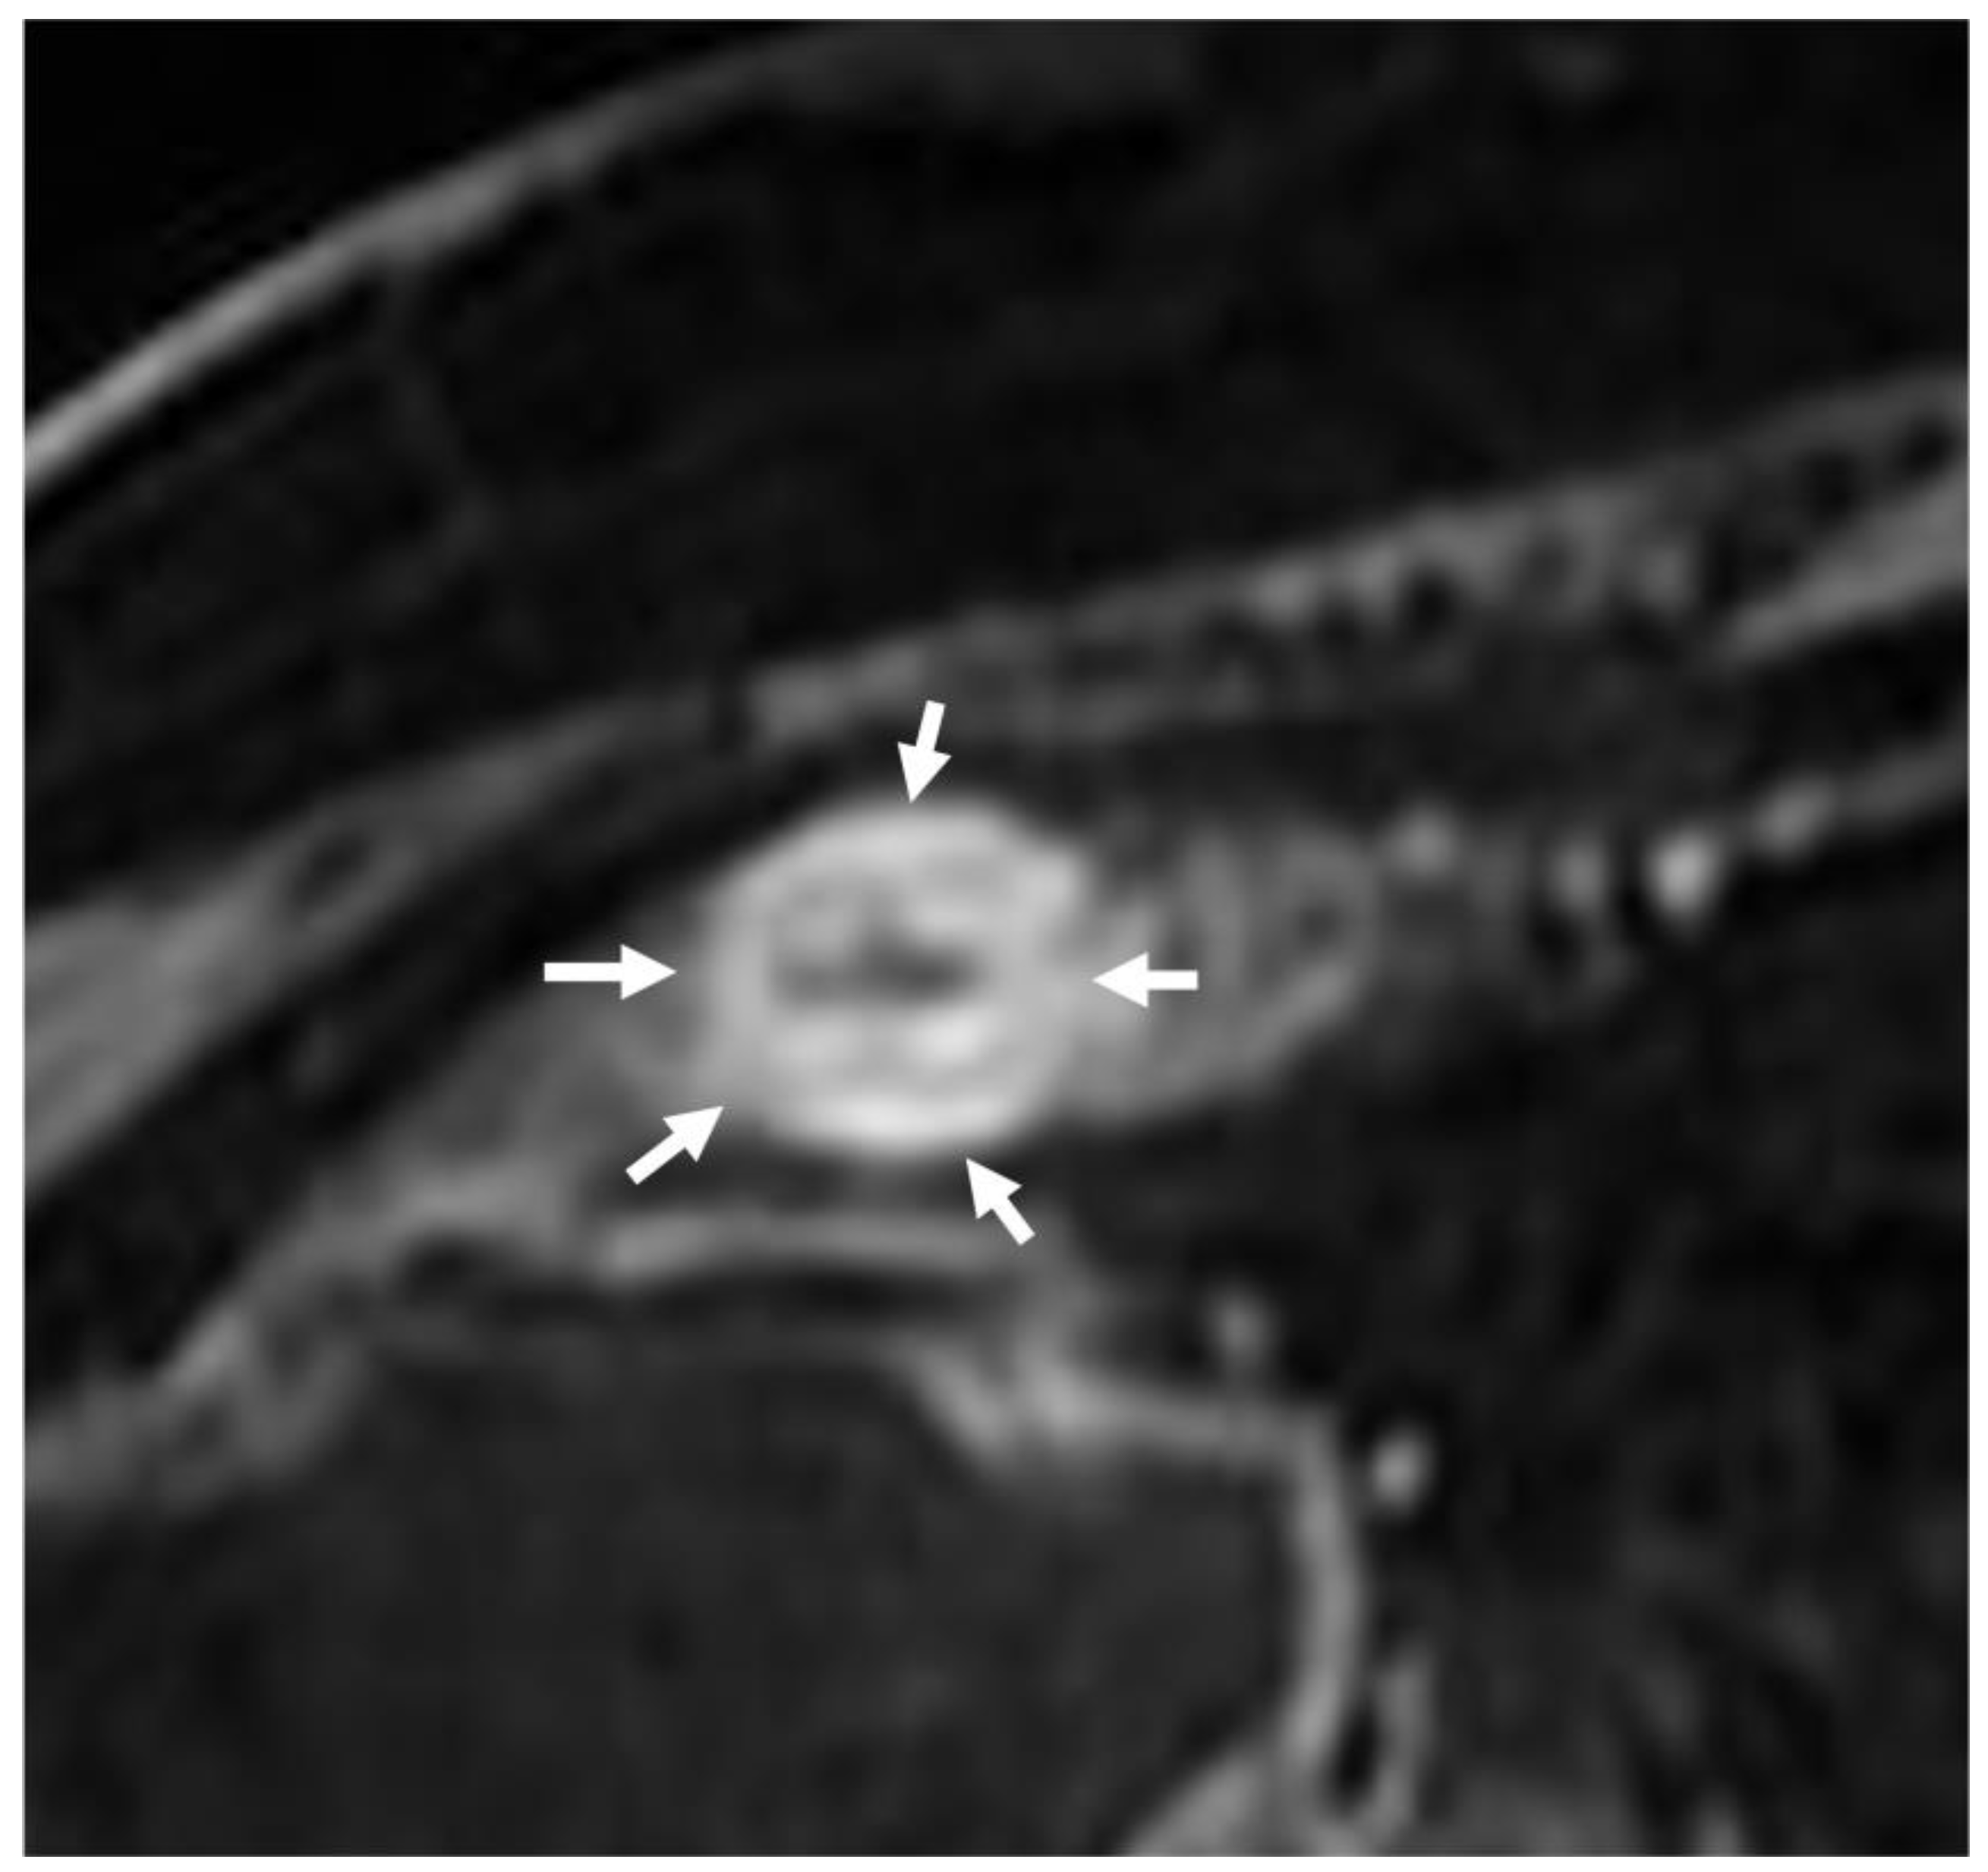

- The wall of a small bowel loop is defined thickened when its thickness (measured from mucosal to serosal layers) is more than 3 mm. According to the degree of thickness, small bowel thickening is defined as “mild” if the thickness is less than 1 cm, “moderate” if it is between 1 cm and 2 cm, and “marked” if it is more than 2 cm [20,21].

- The minimum caliber of the lumen of the bowel loop affected by the stricture is typically considered pathological if it is less than 10 mm at the site of bowel wall thickening or if it is less than 50% compared to the adjacent bowel tracts [23]. Obviously, a correct valuation of this caliber presupposes good bowel preparation, in order to exclude false positives due to inadequate bowel loop distension.